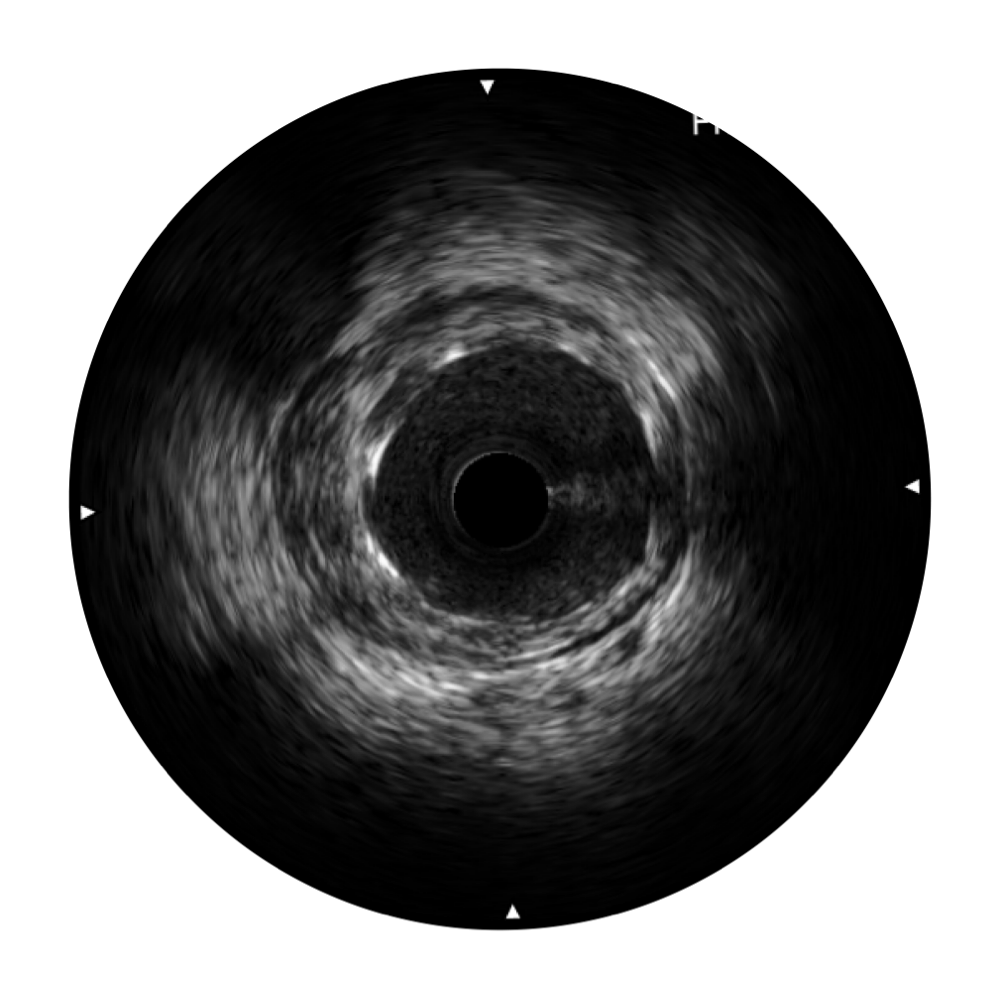

• 球速体育入口宽频IVUS图像

• 传统IVUS图像

对比传统IVUS导管成像,球速体育入口宽频IVUS图像的近场支架梁显影更细腻,远场中膜外血管仍清晰可辨,兼顾远中近,兼顾分辨力与穿透深度